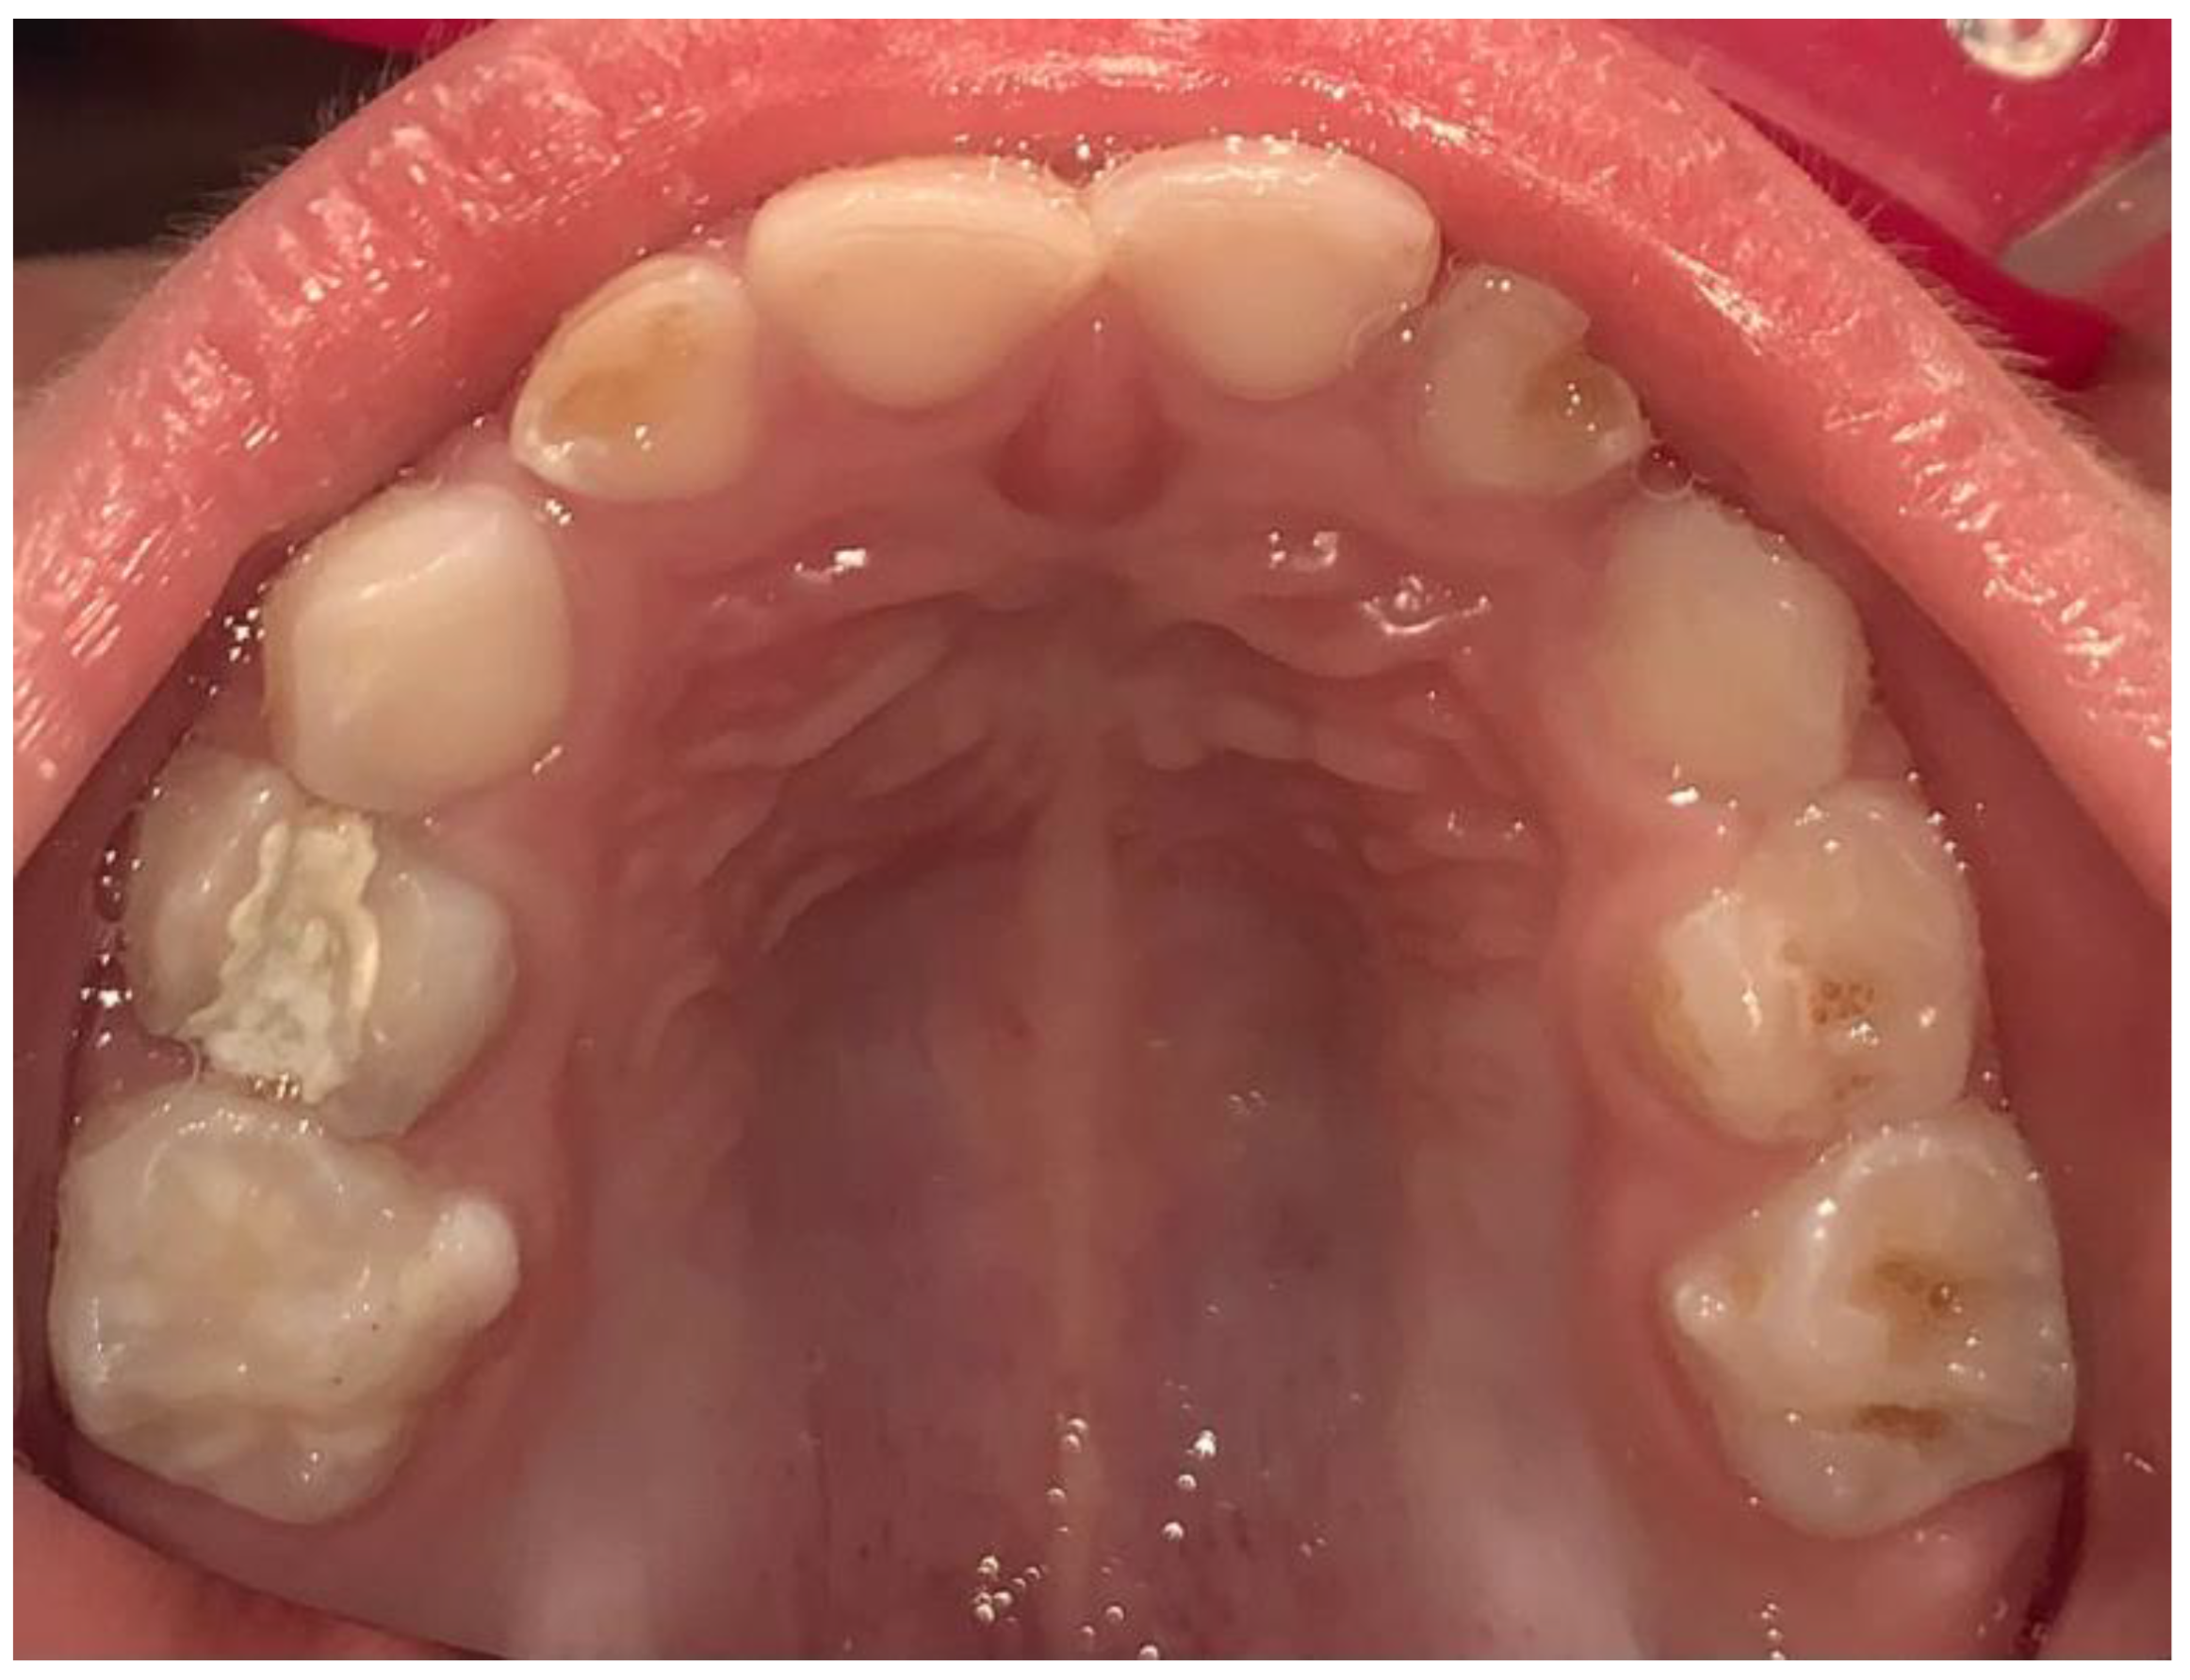

- Wambier, D.S.; Chibinski, A.C.R.; Wambier, L.M.; de Lima Navarro, M.F.; Banerjee, A. Minimum Intervention Oral Care Management of Early Childhood Caries: A 17-Year Follow-up Case Report. Eur. J. Paediatr. Dent. 2023, 24, 20–29. [Google Scholar] [CrossRef]